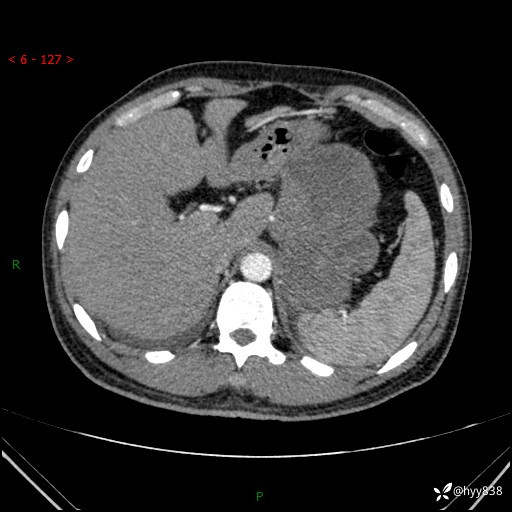

病例39岁/女,左侧腰痛入院。腹腔囊实性肿块,定位、定性---结果公布~

性别:男

年龄:39岁

简要病史:左侧腰痛待查,CT发现腹腔占位

腹部CT平扫+增强